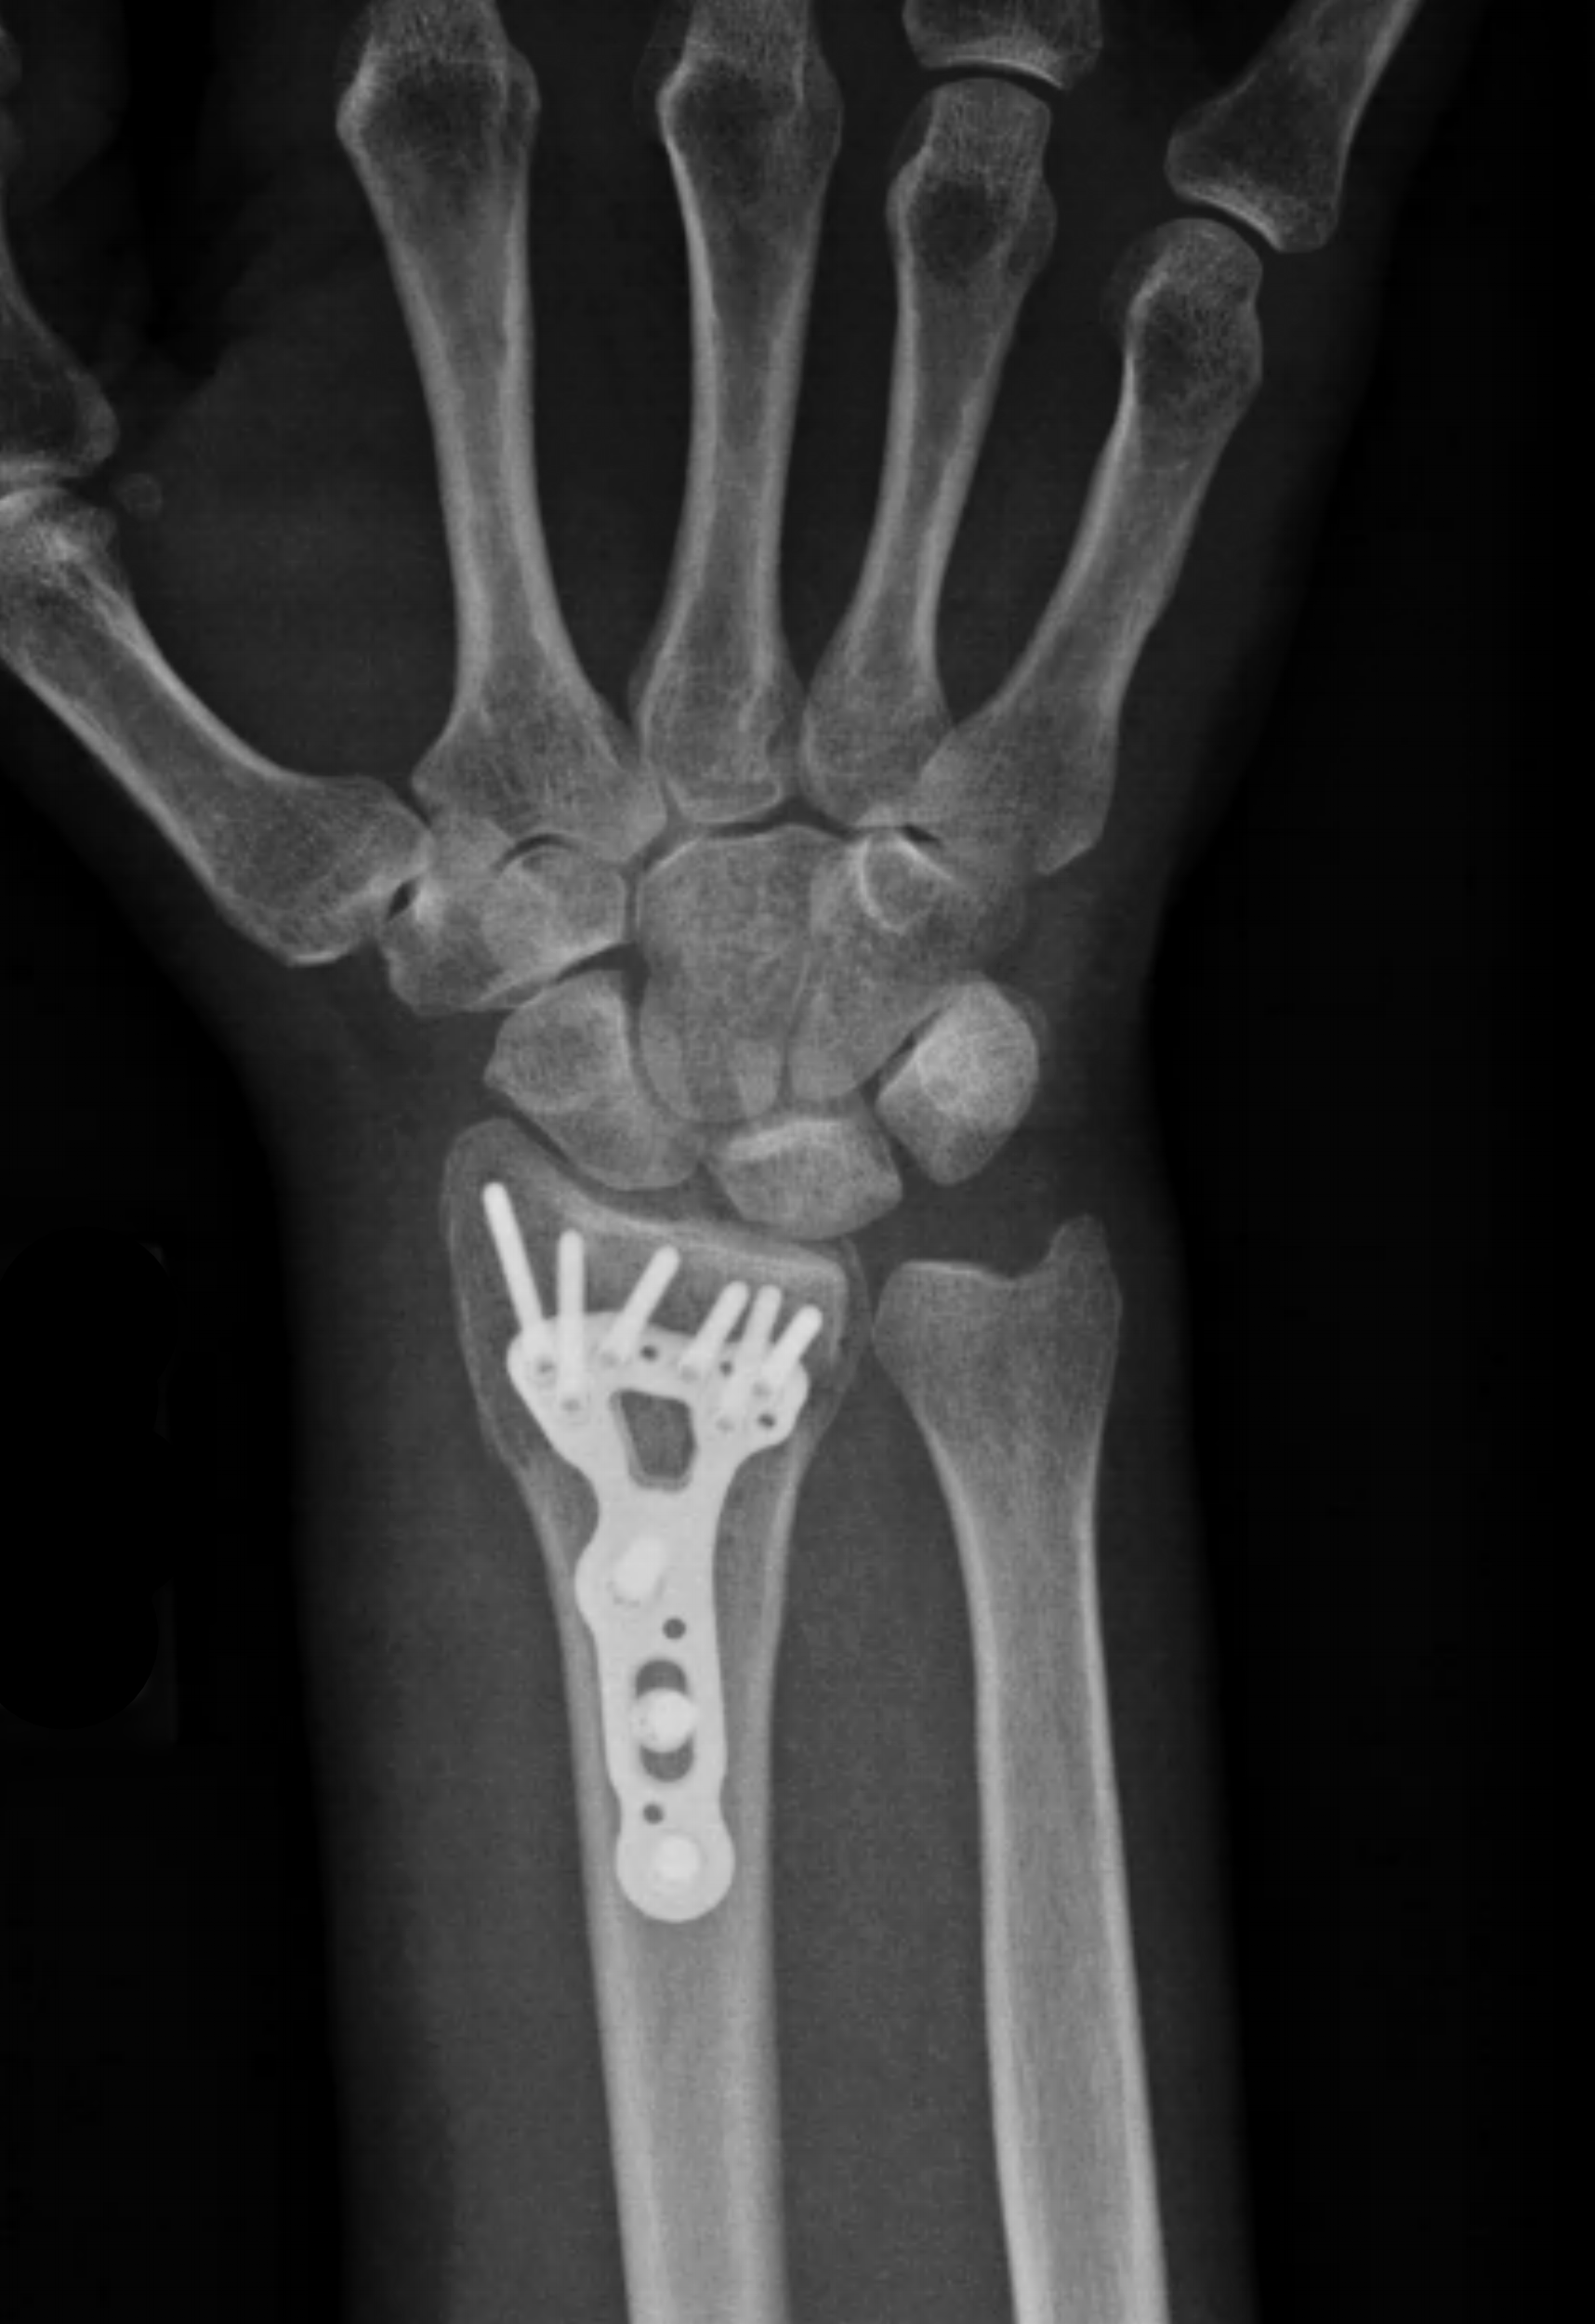

Distal Radius Fracture Raleigh Hand Surgery — Joseph J. Schreiber, MD

Avoiding Distal Radius Fracture Complications (Broken Wrist) (2023)